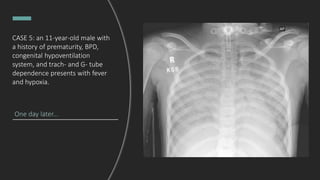

CASE 5: an 11-year-old male with

a history of prematurity, BPD,

congenital hypoventilation

system, and trach- and G- tube

dependence presents with fever

and hypoxia.

What do you see?

- Tracheostomy tube in the upper

third of the thoracic trachea.

- Scattered patchy

alveolar opacities throughout the

mid and lower left lung.

Hospital day 10:

How has the CXR progressed?